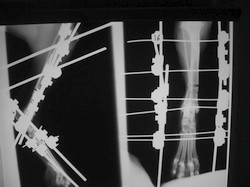

PRÁCTICAS CURSO DE FIJACIÓN EXTERNA PERFECCIONAMIENTO.

Artrodesis tarso.